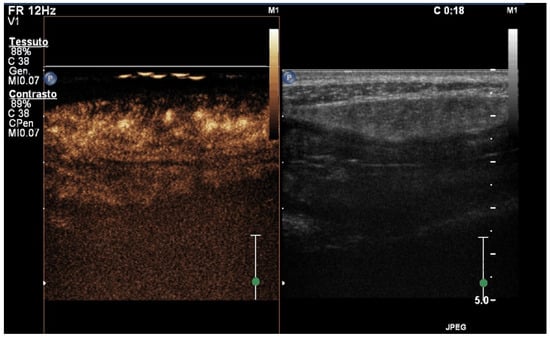

5. Contrast-Enhanced Ultrasound (CEUS)

- Medellin, A.; Merrill, C.; Wilson, S.R. Role of contrast-enhanced ultrasound in evaluation of the bowel. Abdom. Radiol. 2018, 43, 918–933. [Google Scholar] [CrossRef]

- Versluis, M.; Stride, E.; Lajoinie, G.; Dollet, B.; Segers, T. Ultrasound Contrast Agent Modeling: A Review. Ultrasound Med. Biol. 2020, 46, 2117–2144. [Google Scholar] [CrossRef] [PubMed]

- Paratore, M.; Garcovich, M.; Ainora, M.E.; Riccardi, L.; Gasbarrini, A.; Zocco, M.A. Dynamic contrast enhanced ultrasound in gastrointestinal diseases: A current trend or an indispensable tool? World J. Gastroenterol. 2023, 29, 4021–4035. [Google Scholar] [CrossRef] [PubMed]

- Migaleddu, V.; Scanu, A.M.; Quaia, E.; Rocca, P.C.; Dore, M.P.; Scanu, D.; Azzali, L.; Virgilio, G. Contrast-enhanced ultrasonographic evaluation of inflammatory activity in Crohn’s disease. Gastroenterology 2009, 137, 43–52. [Google Scholar] [CrossRef] [PubMed]

- Serafin, Z.; Białecki, M.; Białecka, A.; Sconfienza, L.M.; Kłopocka, M. Contrast-enhanced Ultrasound for Detection of Crohn’s Disease Activity: Systematic Review and Meta-analysis. J. Crohn’s Coli. 2016, 10, 354–362. [Google Scholar] [CrossRef]

- Ripollés, T.; Rausell, N.; Paredes, J.M.; Grau, E.; Martínez, M.J.; Vizuete, J. Effectiveness of contrast-enhanced ultrasound for characterisation of intestinal inflammation in Crohn’s disease: A comparison with surgical histopathology analysis. J. Crohn’s Coli. 2013, 7, 120–128. [Google Scholar] [CrossRef] [PubMed]

- Laterza, L.; Ainora, M.E.; Garcovich, M.; Galasso, L.; Poscia, A.; Di Stasio, E.; Lupascu, A.; Riccardi, L.; Scaldaferri, F.; Armuzzi, A.; et al. Bowel contrast-enhanced ultrasound perfusion imaging in the evaluation of Crohn’s disease patients undergoing anti-TNFα therapy. Dig. Liver Dis. 2021, 53, 729–737. [Google Scholar] [CrossRef] [PubMed]